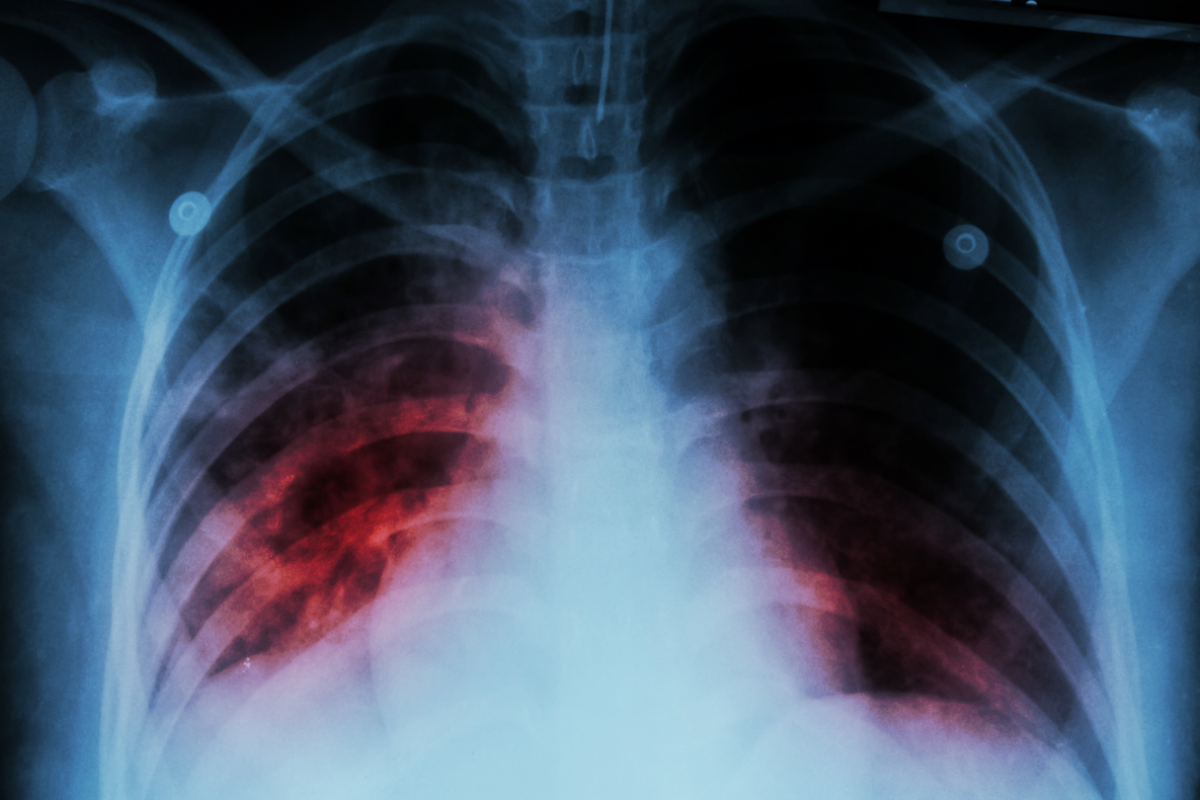

Azərbaycanda 2025-ci ildə 198 uşaqda vərəmə yoluxma halı aşkarlanıb.

Onun sözlərinə görə, Azərbaycanda vərəmə yoluxmada müsbət göstərici müşahidə olunur: "Əgər 2015-ci ildə 436 uşaqda aktiv vərəm xəstəliyi aşkarlanırdısa, 2025-ci ildə bu say 198-ə düşüb".

İ.Axundova onu da qeyd edib ki, 10 il bundan əvvəl hər min nəfərdə 45-42 vərəm faktı aşkarlanırdısa, 2025-ci ildə bu say 21-25-dir.